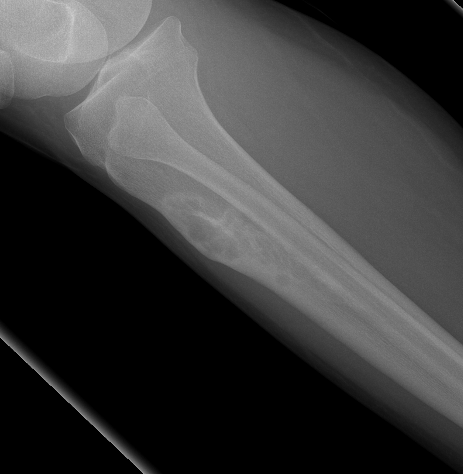

X-ray

Multiple small radiolucent lesions surrounded by sclerosis

Thickened cortex

Doesn't progress on xray

Most common anterior cortex of tibia

Soap-bubble appearance

Eccentrically located

- well circumscribed

- slightly expansile

- cortical thickening

- little or no periosteal reaction